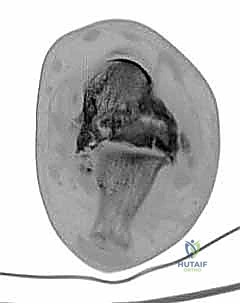

3. استئصال العظام التالفة (Talectomy)

في حالات "شاركو" المتقدمة، تكون عظمة الكاحل (Talus) مجرد فتات عظمي ميت (Avascular Necrosis). يتم استئصال هذه العظمة بالكامل، بالإضافة إلى إزالة أي غضاريف متبقية من أسفل قصبة الساق وأعلى عظمة الكعب لضمان تلامس عظمي حيوي ونظيف.

4. تحضير قصبة الساق وعظمة الكعب

بعد إزالة العظام التالفة، يتم تسوية سطح عظمة قصبة الساق (Tibia) وعظمة الكعب (Calcaneus) بحيث يتطابقان تماماً. هذه الخطوة حاسمة لضمان استقامة القدم (Alignment) وتجنب أي قصر زائد في طول الطرف.